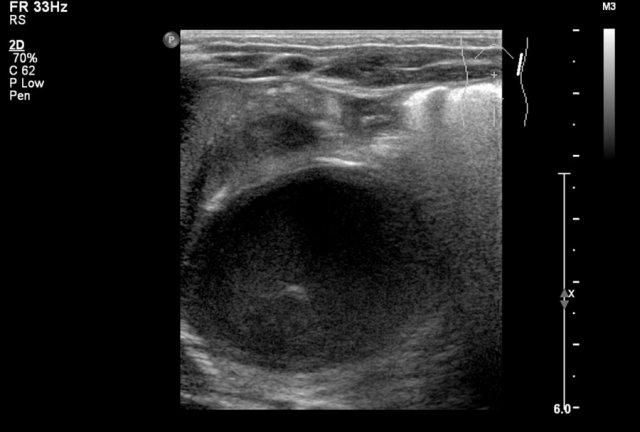

Một bé trai 1 tuổi được chuyển đến với chẩn đoán u nguyên bào thận dạng nang.

Siêu âm phát hiện một nang lớn ở trung tâm ổ bụng.

Khi khảo sát từ hông trái bằng đầu dò tuyến tính tần số cao, có thể thấy một ít mô nhu mô bao quanh các đài thận giãn rất to. Hình ảnh này phù hợp với ứ nước thận mức độ nặng.

Ban đầu, người ta cho rằng có một số thành phần đặc trong nang.

Tuy nhiên, khi ấn đầu dò, các thành phần này được xác định là cặn lắng.

MRI cho thấy hình ảnh tổng quan hơn về tình trạng ứ nước thận.

Nguyên nhân là do hẹp khúc nối bể thận – niệu quản.

Thận trái có chức năng phân chia 33% trên xạ hình thận.

Phẫu thuật tạo hình bể thận đã được thực hiện thành công.